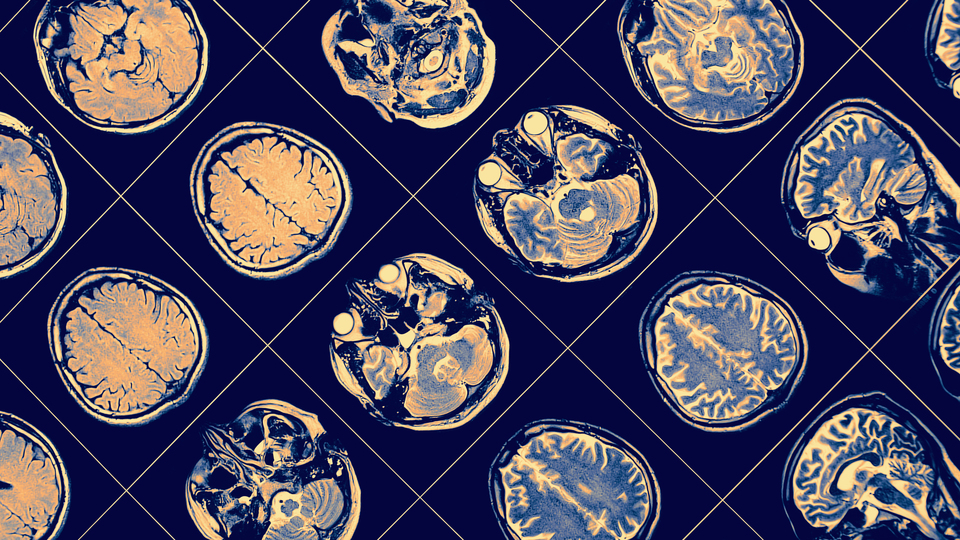

Talihsiz kadın, ilk önce burnunda çıkan bir yara nedeniyle hastaneye gitmişti. Doktorlar bunun basit bir kızarıklık olduğunu düşündü ve antibiyotik ile merhem reçete etti. Ancak kadının şikayeti geçmedi. Bir yıl boyunca dermatologa gitmeye devam etti. Bu süreçte kadının vücudunun sol tarafı titremeye başladı ve en sonunda sol kolunu zayıflatan bir nöbet geçirdi. Doktorlar, BT taramasında kadının beyninde bir tümör olabileceğini gösteren anormal bir lezyon gördü. Bu nedenle doktorlar test için bir doku örneği aldı. Sonraki birkaç gün yapılan ek taramalar, kadının beynindeki olumsuzluğun daha da kötüleştiğini ortaya çıkardı. Kitle büyüyordu ve yeni lezyonlar ortaya çıkıyordu.

Son olarak bir beyin cerrahı, kadının beynini incelemek için kafatasını açtı ve hastanın amip ile enfekte olduğunu buldu.